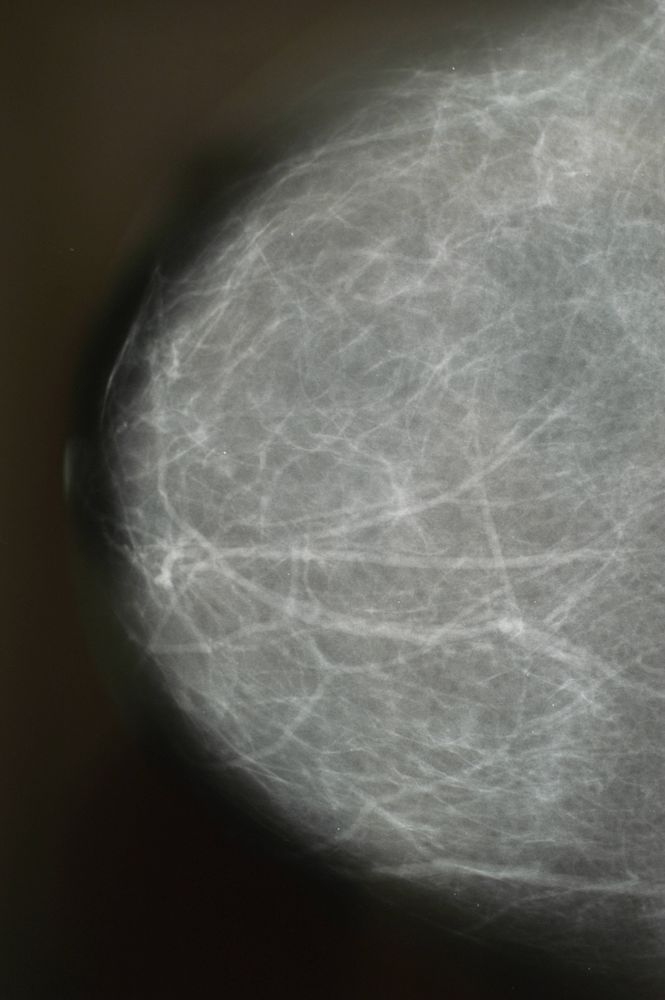

Roentgenaufnahme, Brustroentgen Mammographie einer Frau

IMAGO / blickwinkel

Wie sinnvoll ist die Brustkrebs-Früherkennung? Die wichtigsten Fakten im Überblick

Das Mammografie-Screening bleibt umstritten: Für die einen sind zentral organisierte Früherkennungsprogramme der Schlüssel zum Sieg über den Krebs, für die anderen überwiegen Nachteile und Kosten. Ein Blick auf die nüchterne wissenschaftliche Evidenz.